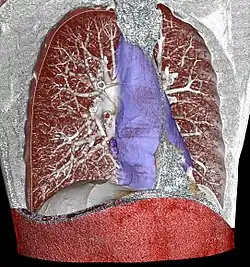

CT scan of a patient with Descending Necrotizing Mediastinitis.

Acute mediastinitis can be confirmed by contrast x-rays since most cases of acute mediastinitis are due to esophageal perforation. Other studies that can be used include endoscopic visualization, Chest CT scan with oral and intravenous contrast.

With regards to CT Imaging, the extent of involvement of the mediastinum can be evaluated. Therefore, acute mediastinitis can be classified into three categories:[9]

1. diffuse mediastinitis

2. isolated mediastinal abscess

3. mediastinitis or mediastinal abscess complicated by empyema or subphrenic abscess.